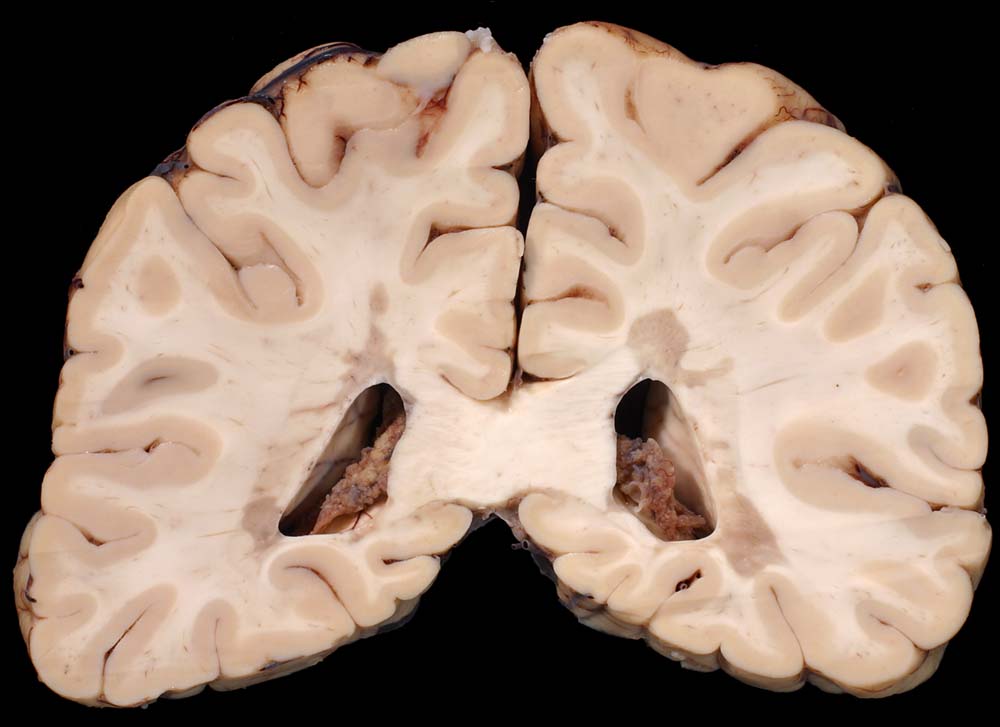

An Frontalschnitten durch das Gehirn fallen makroskopisch Entmarkungsherde vor allem im unmittelbar periventrikulären Marklager auf (um die Vorderhörner, die Cella media und um die Hinterhörner). Nicht selten finden sie sich auch um den Aquädukt und am Boden des 4. Ventrikels. Die Farbe der Herde hängt vom Alter des Prozesses ab (eher rosa bei frischen, eher grau bei alten Herden), die Konsistenz ist weich bei frischen, zunehmend derb bei alten Herden durch Gliafaservermehrung. Histologisch zeigen frische Entmarkungsherde in den ersten Tagen eine Oligodendrogliavermehrung. Ihr folgt mit beginnendem Markabbau eine Mikrogliareaktion. Mikrogliazellen, Monozyten und Makrophagen phagozytieren die Markscheidenzerfallsprodukte (> 10160) (> 10159), die teilweise lichtmikroskopisch im Zytoplasma erkennbar sind (> 10161). Lymphozyten und Plasmazellen sind vor allem perivenös an den Herdrändern lokalisiert. Zusätzlich proliferieren faserbildende Astrozyten (> 10162). In älteren Herden (vorliegendes Präparat) fehlen die Markscheiden praktisch vollständig. Axone bleiben erhalten und es besteht eine dichte Fasergliose. Diese ausgebrannten Herde überwiegen beim chronisch Erkrankten. Auch bei ihm können allenfalls noch frischere Stadien gefunden werden.

Makroskopie

Befund

Pathologischer Befund

Normalbefund